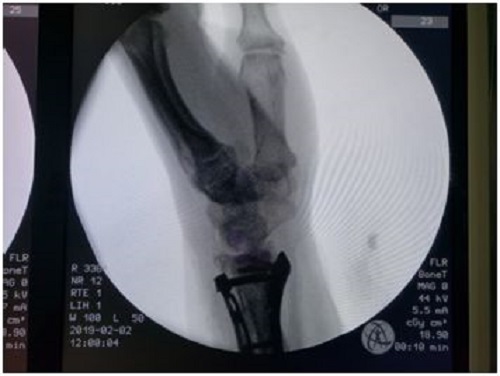

利用3个手术间,成功完成8台手术!